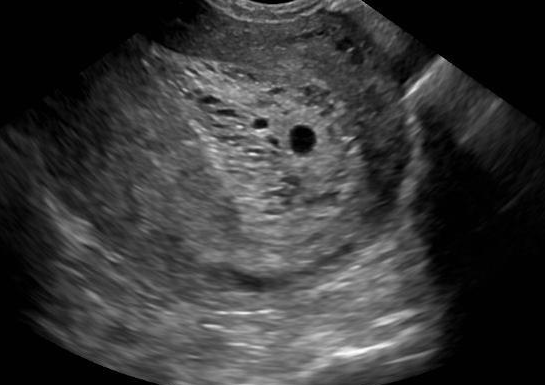

Example 2: restoration of images corrupted by blur and SPN or AWLN. In this example we evaluate the performance of the proposed TV-L1 model on three medical test images lungs (), Fig. 5 (a), ecography (), Fig. 6 (a), and aneurism (), Fig. 7 (a), synthetically corrupted by Gaussian blur of parameters band=5 and sigma=1 and by two types of impulsive noise, namely SPN and AWLN.

The images are provided in the repository at https://medpix.nlm.nih.gov.

| (a) original | (b) TV-L1 (ISNR = 22.13) | (c) zoom of (b) |

![]() |

| (d) corrupted | (e) TVp-L1 (ISNR = 23.15) | (f) zoom of (e) |

| (g) -map () | (h) TV-L1 (ISNR = 25.46) | (i) zoom of (h) |

| (l) -map () | (m) TV-L1 (ISNR = 28.01) | (n) zoom of (m) |

First, for what concerns corruptions by SPN, in Figs. 5, 6, 7 we report for the three considered test images the original and corrupted image together with the estimated -maps in the first column (with the size of the neighborhoods used for the -maps estimation reported in the captions), the restoration results, obtained by the four compared methods, in the second column (with the achieved ISNR values in the captions) and a zoomed detail of the restored images - green- bordered in Figs. 5 (a), 6 (a), 7 (a) - in the last column.

The reported ISNR values as well as the visual inspection of the restored images and of the zoomed details strongly indicate how the proposed space-variant regularizer allows for higher quality restorations. In particular, it is worth remarking how, with respect to the space-variant TV model, the additional degrees of freedom represented by the scale parameters used in our proposal, yield a sufficient additional flexibility for avoiding unwanted spurious effects - see, e.g., spikes in Figs. 5 (i), 6 (i), 7 (i).